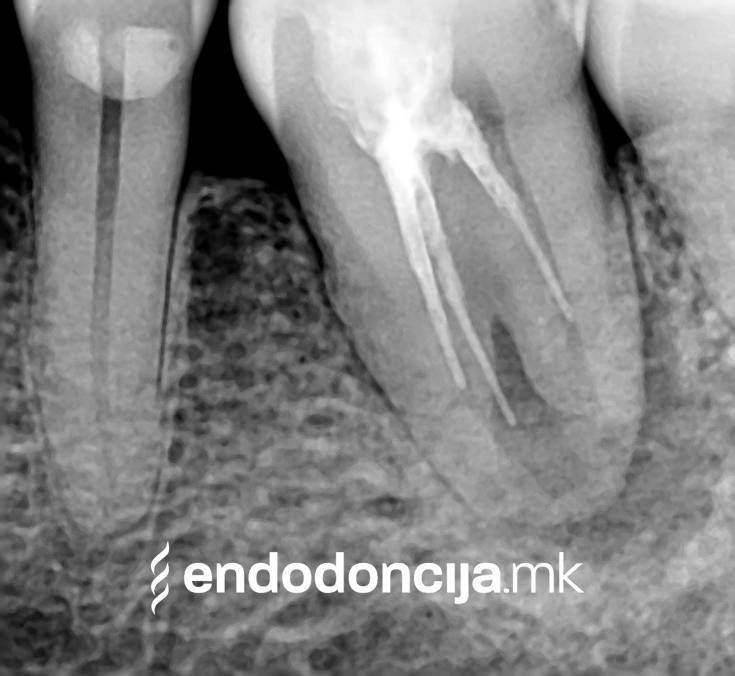

Σε περίπτωση ανανέωσης της θεραπείας του ριζικού καναλιού (αναθεώρηση) παλιά γεμίσματα ρίζας που δεν ήταν επιτυχημένα και ως εκ τούτου ήταν η αιτία φλεγμονών και πόνου, μπορούν να αφαιρεθούν και να ανανεωθούν εξειδικευμένα. Αυτή η θεραπεία εξαλείφει τις φλεγμονές στην περιοχή της ρίζας και καθίσταται δυνατή η πλήρης ανάρρωση.

Εκτός από την ανίχνευση των ριζικών καναλιών, η ενδελεχής προετοιμασία και η απολύμανση του ριζικού σωλήνα είναι η προϋπόθεση για μια επιτυχημένη συνολική θεραπεία. Μέσω της χρήσης των νεότερων οργάνων και αντιβακτηριακών διαλυμάτων, όλα τα υπολείμματα ιστών και τα βακτήρια που υπάρχουν μπορούν να εξαλειφθούν.

Οι υπηρεσίες του Ειδικού Τμήματος Ενδοδοντικής δεν περιορίζονται καθόλου στη συμβατική επεξεργασία ριζικών καναλιών. Αντιμετωπίζουμε αποκλειστικά τους ασθενείς μας με τα νεότερα υλικά και όργανα με μικροσκόπιο, προκειμένου να είμαστε σε θέση να καθαρίσουμε εντελώς και να προετοιμάσουμε όλα τα κανάλια πριν τα γεμίσουμε.